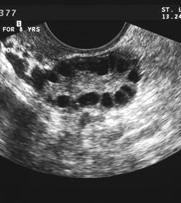

Polycystic Ovary Syndrome (PCOS)